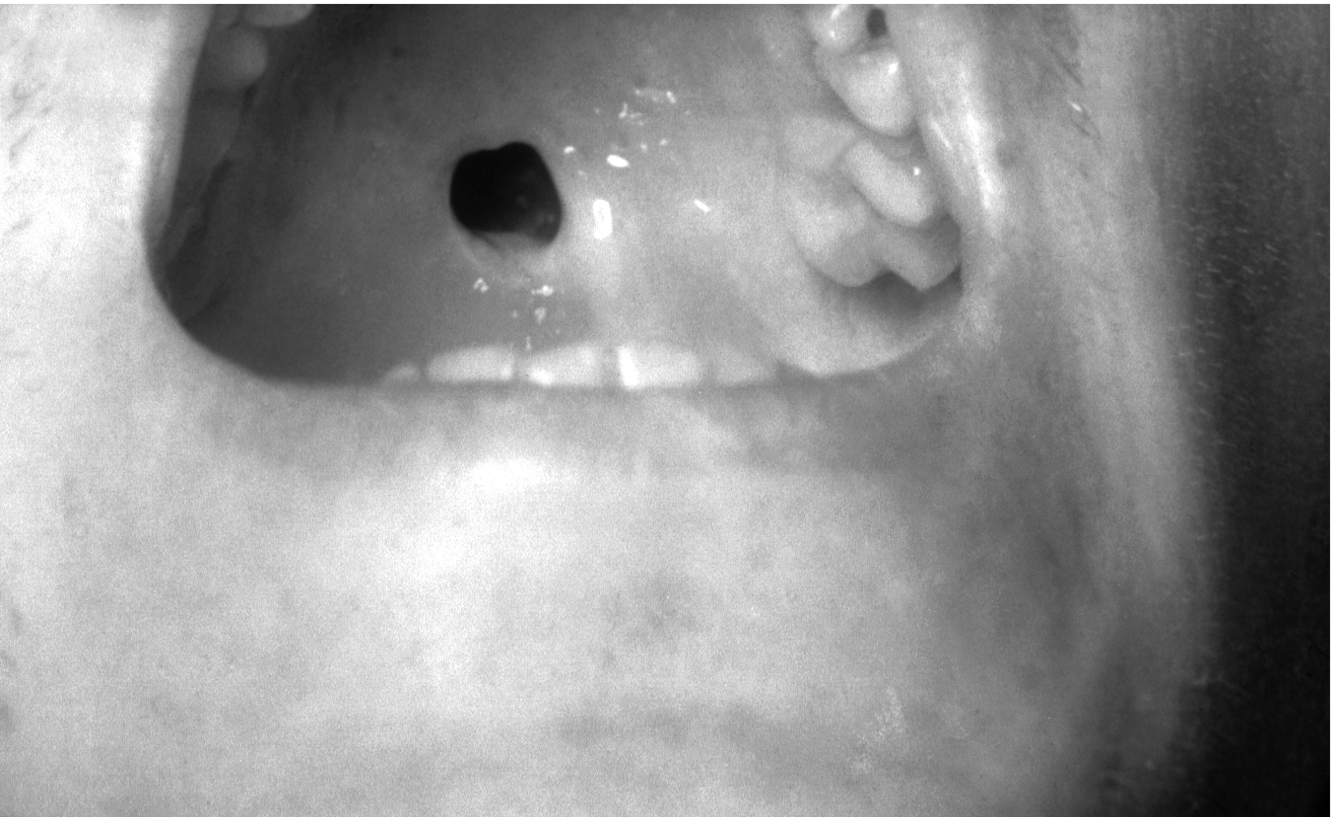

Primary Syphilis

• Painless chancre (like an ulcer) at the site of infection.

• Occurs on the body where the spirochete enters. Often on the genitals b/c it’s mainly a sexually transmitted disease. Chancre develops 10-90 days after initial infection. It’s painless, so often goes unnoticed. Heals on its own after about a month.

Tertiary Syphilis

• Effects of long-term tissue desctruction

• Gumma - a mass of dead and swollen tissue, often found in the mouth.